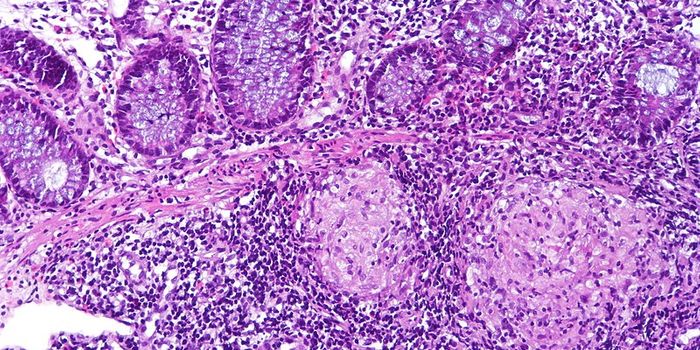

MAR 04, 2019Health & MedicineSarcoidosis is a rare, granulomatous disease that is found in the lungs of 90% of people diagnosed, but it can affect an ...